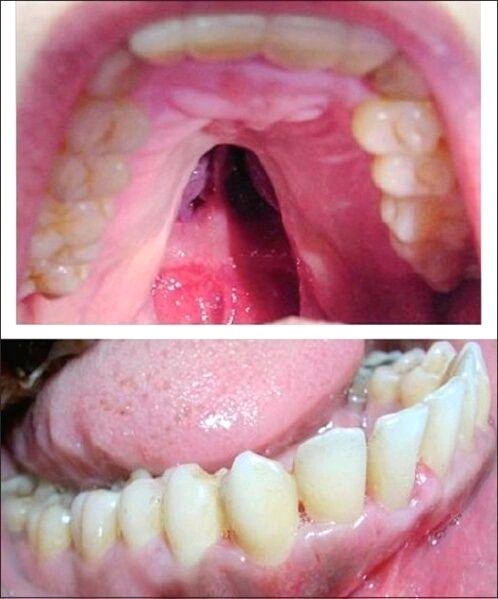

唇腭裂分为唇裂和腭裂,唇裂、腭裂可单独出现,也可相伴发生。

唇裂有损患儿容貌,腭裂会影响患儿发音,唇腭裂患者可能出现上颌骨发育不良,牙槽嵴裂的患者可能存在牙列不齐、咬合异常、牙齿萌出障碍等。唇、腭裂患儿有吸吮困难,有的容易发生上呼吸道感染,有些还容易罹患耳朵的疾病。由于容貌的缺陷、发音的障碍,随着年龄增长,这些孩子往往出现严重的心理问题。所以,患有唇腭裂必须尽早治疗。

唇腭裂是一种较常见的唇部畸形,选择治疗时机格外重要。